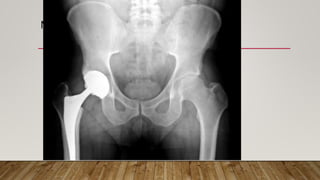

This document discusses radiology and the use of x-rays. It begins with an introduction to radiology and x-rays, noting their importance as the "father of medical investigations." It then discusses anatomy as seen on radiographs and whether x-rays are enough. The document goes on to compare gross views to radiological views, noting what each can and cannot show. It highlights important figures in the development of radiology, from x-rays to CT, MRI, and ultrasound. Specific anatomical structures visible on upper and lower limb x-rays are listed. The document concludes by discussing how pathologies appear on x-rays and the importance of clinical history and knowledge when interpreting radiological images.